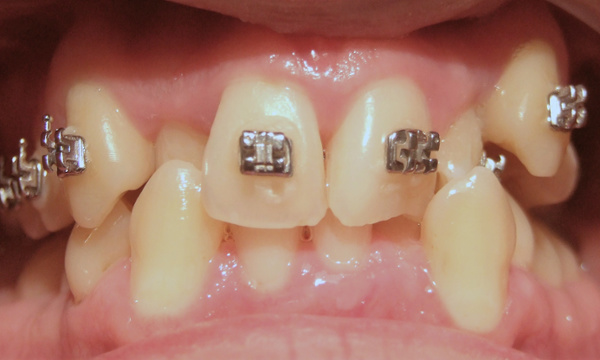

Not all orthodontic journeys start on the right path. This patient came to us with partial braces and a desire for clinical excellence. Dr. Martinez accepted the challenge, providing the expert, hands-on care necessary to "rescue" this complex case. After 24 months of specialized treatment in our Miami orthodontic practice, we achieved a healthy, stable, and properly aligned smile. Experience the difference 35 years of expertise makes.